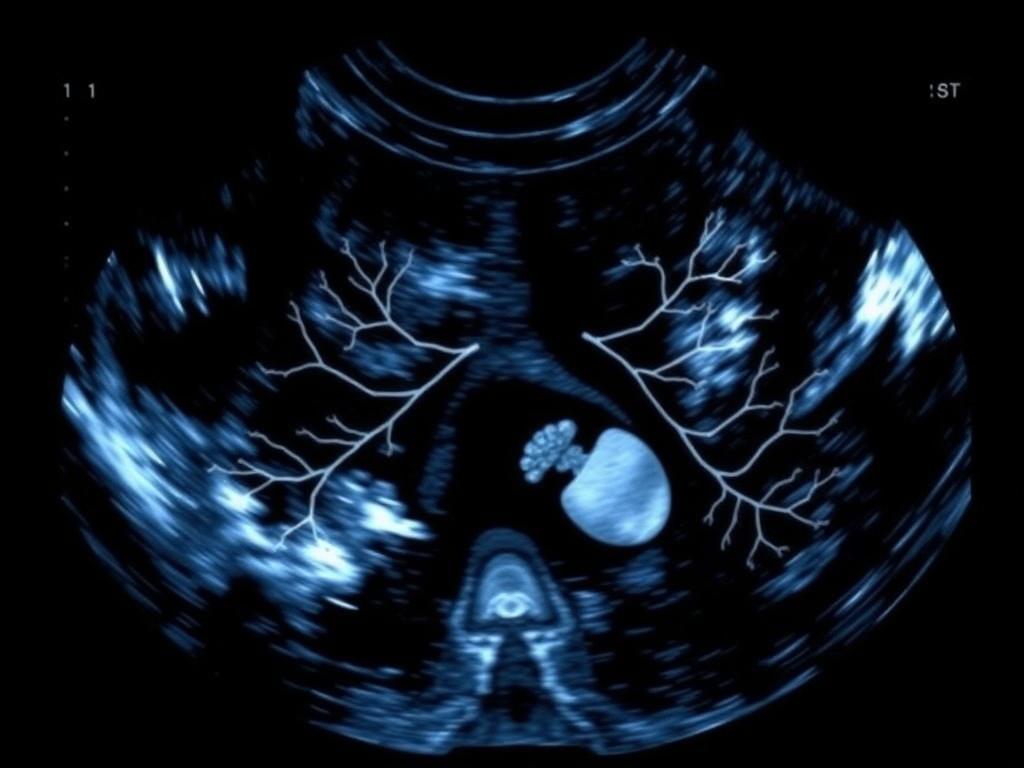

Das Organscreening, oft als „Feinultraschall“ bezeichnet, ist eine gründliche sonografische Untersuchung des ungeborenen Kindes. In Deutschland wird sie in der Regel zwischen der 19. und 22. Schwangerschaftswoche angeboten, weil dann viele Strukturen gut sichtbar sind.

Anders als die Basisuntersuchungen dient das Screening nicht primär der Messung von Wachstum, sondern der gezielten Darstellung von Organen und Körperstrukturen. Ziel ist, Auffälligkeiten früh zu erkennen und geplante Schritte zur weiteren Abklärung zu ermöglichen.

Beim Screening werden viele Bereiche systematisch durchgegangen: Gehirn, Herz, Wirbelsäule, Gesicht, Bauchwand, Magen, Nieren, Harnblase, Extremitäten, Plazenta und Versorgung durch die Nabelschnur. Auch die Menge des Fruchtwassers gehört zur Beurteilung.

Die Darstellung erfolgt nach definierten Richtlinien, damit Auffälligkeiten erkannt und dokumentiert werden können. Manche Organe sind besser zu beurteilen als andere; hier spielen Lage, Bewegungen des Kindes und mütterliche Faktoren eine Rolle.